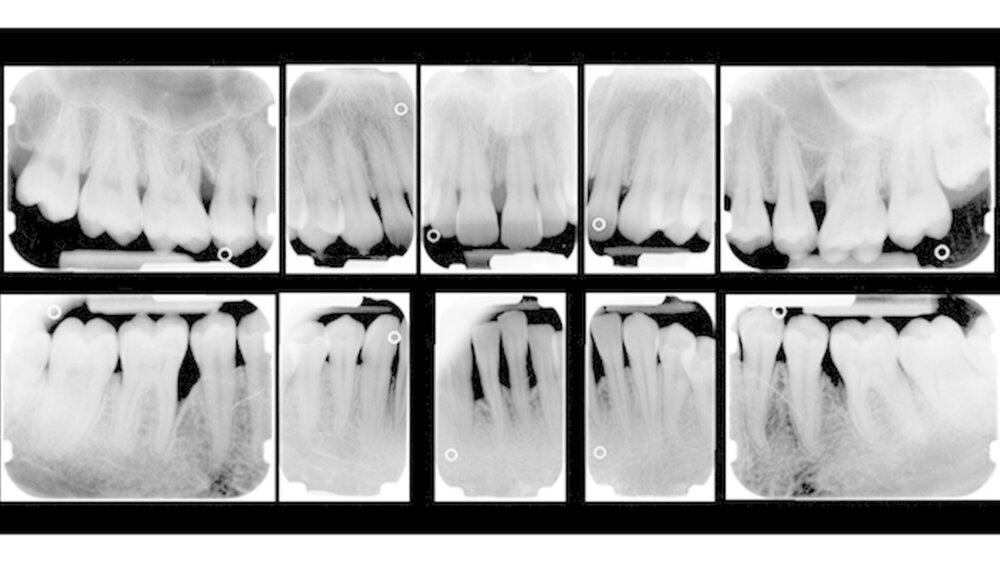

Im Rahmen der Untersuchungen konnten wir zeigen, dass Patienten mit AgP nicht nur kurzfristig, sondern auch über zehn Jahre nach APT stabile parodontale Verhältnisse vorweisen. Mit einer Zahnverlustrate von 0,13 Zähnen/Patient/Jahr und einer 10-Jahres-Überlebensrate von 94,8 Prozent tritt Zahnverlust insgesamt selten bei Patienten mit AgP auf und unterscheidet sich nicht von Zahnverlusten bei Patienten mit ChP. Mehr als 50 Prozent der Probanden erlitten keinen Zahnverlust und nur wenige verloren mehr als drei Zähne.

Zahnverlust tritt demnach auch bei der AgP vor allem bei sogenannten Hochrisikopatienten auf. Auf Patientenebene konnten die Faktoren niedriger Ausbildungsstand, Alter und Abwesenheit des IL-1-Polymorphismus als signifikante Risikofaktoren für Zahnverlust festgestellt werden. Signifikante zahnbezogene Faktoren für Zahnverlust stellten die Punkte hoher initialer Knochenabbau, Lokalisation im Oberkiefer, Zahntyp ‚Molar’ und Pfeilerzahn dar.

Bei etwa einem Viertel der Patienten lag bei Reevaluation ein Rezidiv vor. Als Risikofaktoren für das Auftreten eines Rezidivs konnten Rauchen, ein hoher mittlerer Gingival Bleeding Index (Ainamo & Bay 1975) und hohe nachweisbare Mengen der Parodontalpathogene T. forsythia und T. denticola festgehalten werden. Patienten, die regelmäßig zur UPT erschienen waren hingegen vor Rezidiven geschützt. Ebenso zeigte die Compliance zur UPT einen signifikant positiven Einfluss auf die Kariesinzidenz.